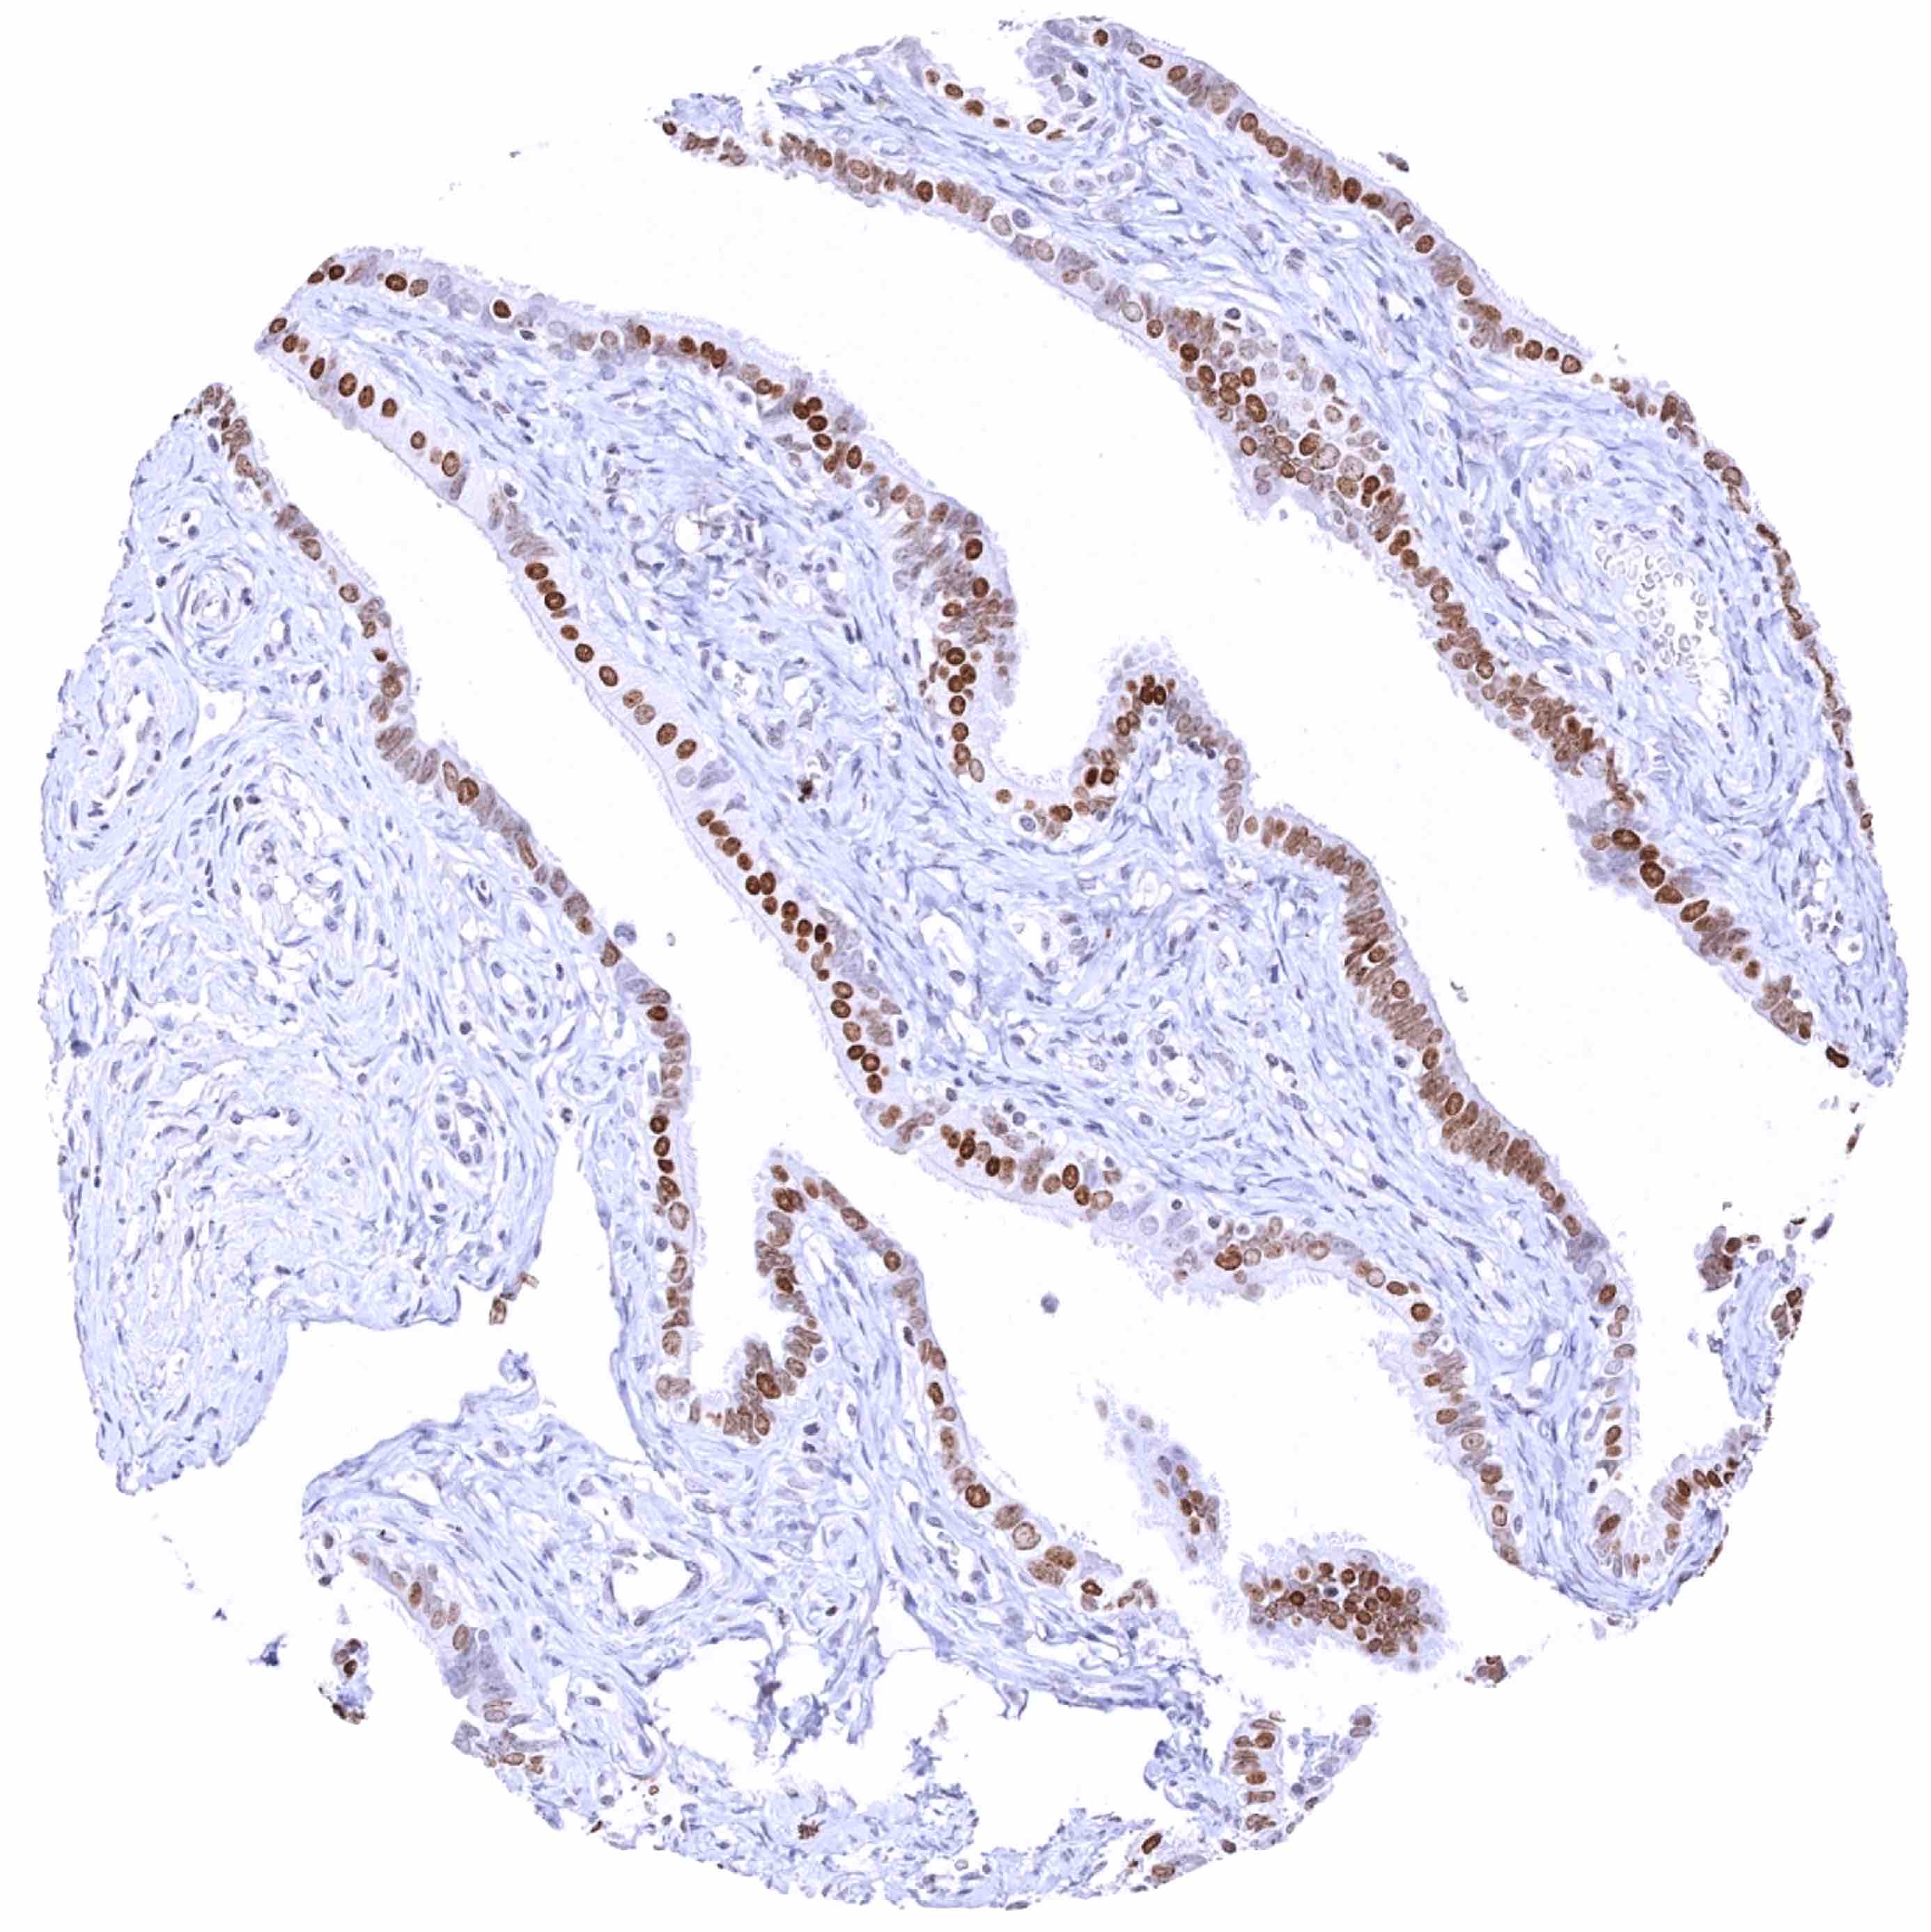

Fallopian tube, mucosa – Moderate to strong nuclear HMGA2 staining of a large subset of epithelial cells

Fallopian tube, mucosa – Strong nuclear HMGA2 staining of most epithelial cells